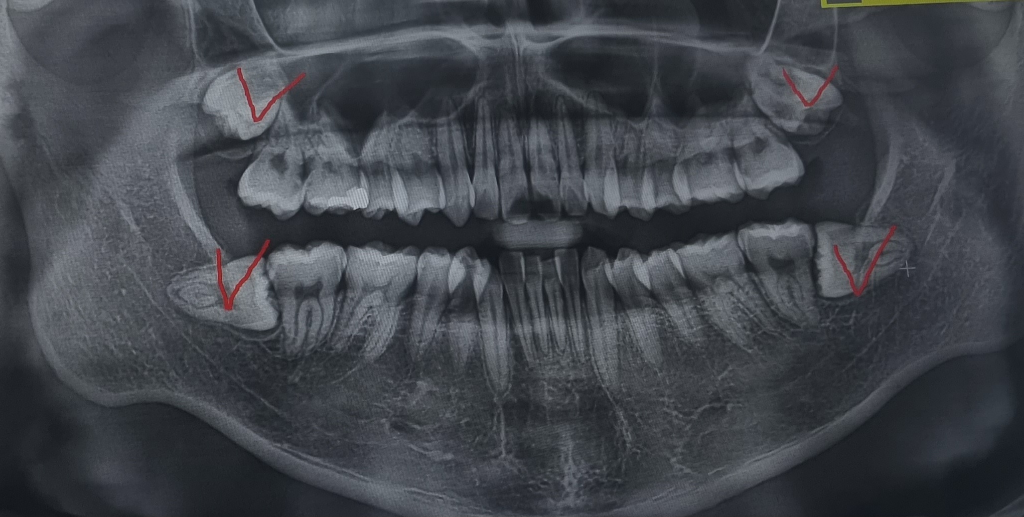

사랑니발치 가격,시기 적당한지 궁금합니다ㅜ

사랑니 4개를 한번에 발치했는데요

궁금한게 있어서 발치 전후 사진도 첨부했습니다

3.발치 전 사진을 보았을때

치아가 좀 더 성장하고 뽑았어야 할까요?

발치시기가 너무 이르진 않았을지 걱정됩니다

발치전

• 1번 째 사진

-아닙니다. 이미 사랑니는 다 성장이 끝난상태입니다.